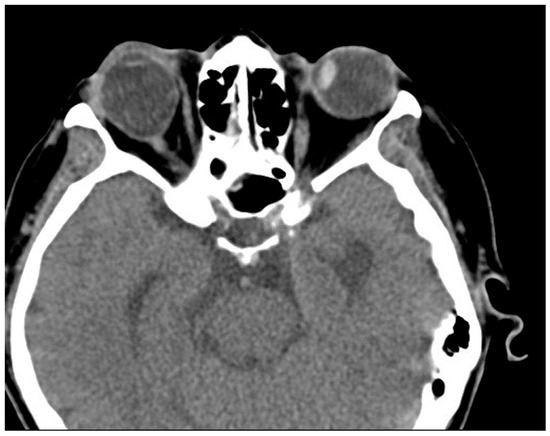

Case 5 was a 67-year-old female who presented with 100 PD ET in the left eye (Figure 5). Her visual acuity was 20/20 in the right eye (SE, −2.125) and hand motion in the left eye (SE, +1.0 D). Twenty years ago, the patient had blunt trauma to her head and lost vision in her left eye. Optic atrophy of the left eye due to traumatic optic neuropathy was observed during the fundus examination. Severe abduction deficit (−4) of the left eye was observed. Preoperative CT was performed and enlarged left medial rectus was noted (Figure 6). During strabismus surgery, severe restriction of the left MR by the forced duction test was noted and the left MR was disinserted accidentally during the procedure. After 1 day, her esodeviation was still 100 PD by MR disinsertion. One month after surgery, esodeviation was 80 PD in her left eye. The patient refused further surgery and was lost during follow-up.

Figure 6. Preoperative CT image of Case 5. Thickening of the left medial rectus muscle with severe left esotropia is noted.